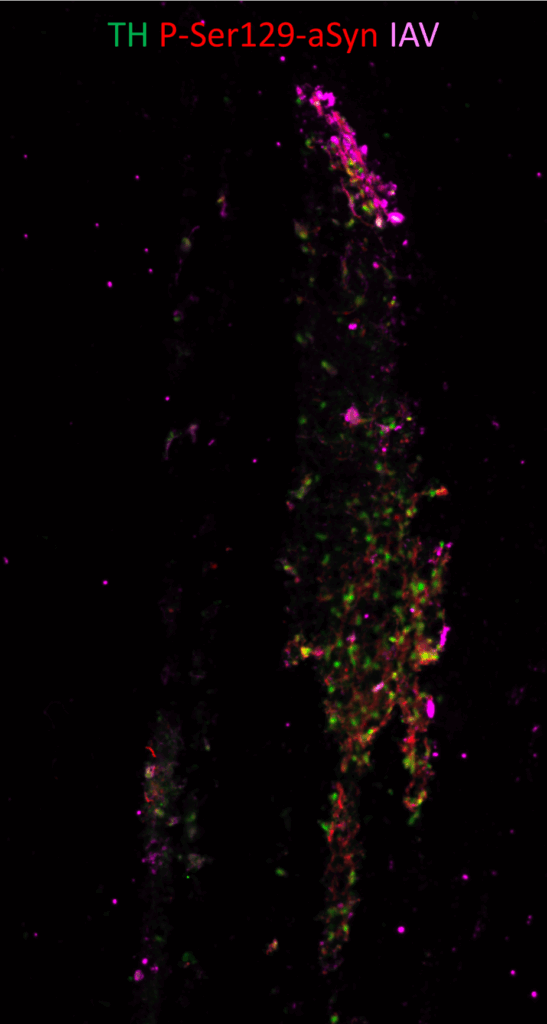

Optimisation et utilisation d’organoïdes mésencéphaliques humains pour élucider les mécanismes moléculaires de l’agrégation de l’alpha-synucléine induite par le virus de la grippe.

Des études épidémiologiques ont établi une association entre la maladie de Parkinson (MP) et l’infection par le virus de la grippe (IAV). Pour établir un lien causal, il est nécessaire de comprendre les mécanismes par lesquels ce virus pourrait causer la maladie. Nos résultats préliminaires suggèrent que IAV induit l’agrégation de la protéine alpha-synucléine (aSyn), un processus crucial dans la pathogenèse de la MP. Les neurones qui dégénèrent lors de la MP étant les neurones dopaminergiques de la substance noire, notre but est d’implémenter et optimiser la culture d’organoïdes mésencéphaliques humains pour modéliser au mieux la MP et étudier par quels mécanismes IAV pourrait induire l’agrégation de l’aSyn.

Coupe d’organoïde mésencéphalique marqué par immunofluorescence avec un anticorps contre IAV, un marqueur de neurone dopaminergique et un marqueur d’agrégation de l’aSyn.